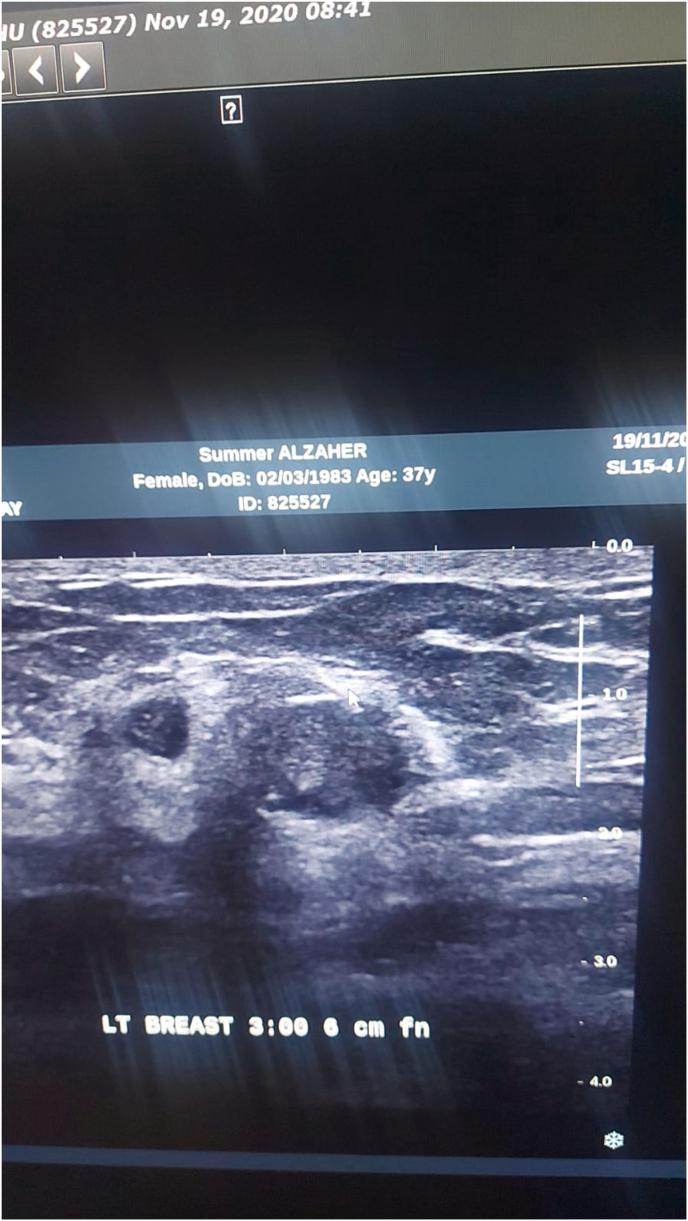

Idiopathic granulomatous mastitis (IGM) is a benign persistent inflammatory breast entity characterized histologically by lobulo centric granulomas. Diagnosis may be difficult and involves a strong index of suspicion. There are plentiful studies are published which render the disease more frequently than expected. The strategy for imaging IGM depends on patient age, clinical manifestations, and risk factors. Patients have an excellent prognosis when they are appropriately treated. The management remains contentious, good judgment is required to ensure optimum treatment form and timing.

特发性肉芽肿性乳腺炎(IGM)是一种良性的持续性乳腺炎症性疾病,组织学特征为小叶中心性肉芽肿。诊断可能困难,需要高度怀疑指数。已有大量研究发表,使该疾病比预期更常见。IGM的影像学检查策略取决于患者年龄、临床表现和危险因素。患者经适当治疗后预后良好。治疗方法仍存在争议,需要良好的判断力以确保最佳的治疗方式和时机。